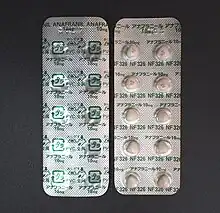

Treatment involves counseling, such as cognitive behavioral therapy (CBT), and sometimes antidepressants, such as selective serotonin reuptake inhibitors (SSRIs) or clomipramine.[4][5] CBT for OCD involves increasing exposure to what causes the problems while not allowing the repetitive behavior to occur.[4] While clomipramine appears to work as well as SSRIs, it has greater side effects and thus is typically reserved as a second-line treatment.[4] Atypical antipsychotics may be useful when used in addition to an SSRI in treatment-resistant cases but are also associated with an increased risk of side effects.[5][8] Without treatment, the condition often lasts decades.[2]

Medication

The medications most frequently used are the selective serotonin reuptake inhibitors (SSRIs).[4] Clomipramine, a medication belonging to the class of tricyclic antidepressants, appears to work as well as SSRIs but has a higher rate of side effects.[4]

SSRIs are a second line treatment of adult obsessive compulsive disorder (OCD) with mild functional impairment and as first line treatment for those with moderate or severe impairment. In children, SSRIs can be considered as a second line therapy in those with moderate-to-severe impairment, with close monitoring for psychiatric adverse effects.[87] SSRIs are efficacious in the treatment of OCD; people treated with SSRIs are about twice as likely to respond to treatment as those treated with placebo.[94][95] Efficacy has been demonstrated both in short-term (6–24 weeks) treatment trials and in discontinuation trials with durations of 28–52 weeks.[96][97][98]